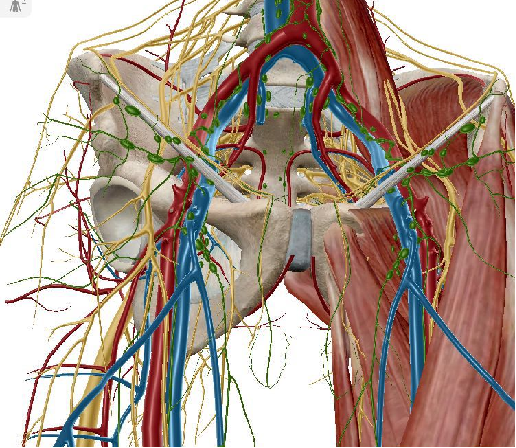

血管:髂血管、股血管、闭孔血管、臀上/下血管、死亡冠(Corona mortis / crown of death,腹壁下血管与闭孔血管的交通支)等。

神经:腰骶丛、股神经、坐骨神经、闭孔神经、臀上神经、股外侧皮神经等。脏器:精索(子宫圆韧带)、膀胱、尿道、阴道、直肠等

死亡冠(Corona mortis / crown of death)髂外血管与闭孔动脉的交通支部分是腹壁下动脉与闭孔动脉的交通支